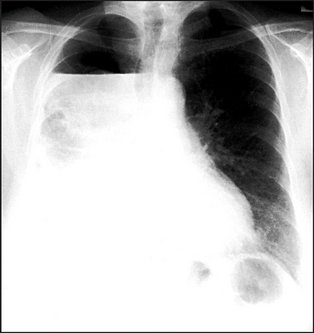

Figure 12.6 Pleural effusion The upper margin of the effusion is curved (‘meniscus sign’). The left hemidiaphragm is not seen because there is no adjacent aerated lung for contrast. The heart shows some deviation to the right. It is unlikely that this is caused by an effusion of this size. It is probably related to the lower thoracic scoliosis.